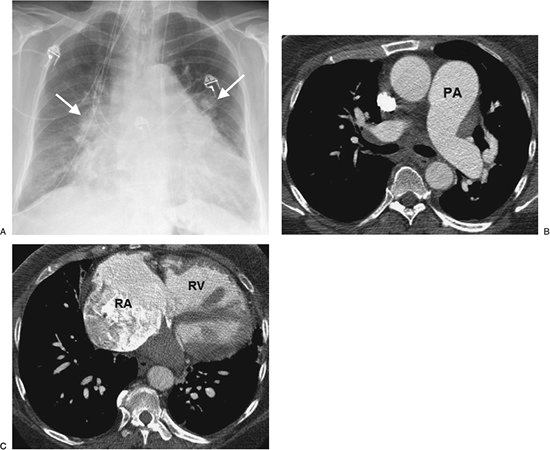

FIGURE 17-27. Primary pulmonary arterial hypertension. A: PA chest radiograph of a 54-year-old woman shows enlargement of the pulmonary arteries (arrows) and cardiac enlargement. B: CT confirms enlargement of the main (PA), right, and left pulmonary arteries. Note that the main pulmonary artery is larger in diameter than the adjacent ascending aorta. Systolic and diastolic pulmonary artery pressures were 97 mm Hg and 53 mm Hg, respectively, with a mean pressure of 70 mm Hg. C: CT at a more inferior level shows enlargement of the right atrium (RA) and right ventricle (RV).